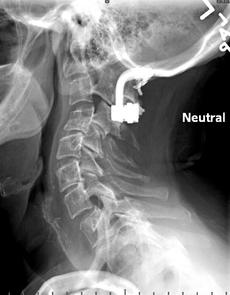

Normal

Plain film of C-spn 15 years post decompression of foramen magnum, placement of a bovine (cow) pericardium sling for ACM, and titanium rod fusion of occiput to C3 (C4 ?)  -  PRE odontoid removal.

My original MRI -   NO clivus. Third cervical vertebra is now at the level of rounded white bone on first picture.  C1 and C2 are way up inside skull and jagged top is offending the brain stem. Initial brainstem width measured 18mm. ACM obscured by artifact from titanium.